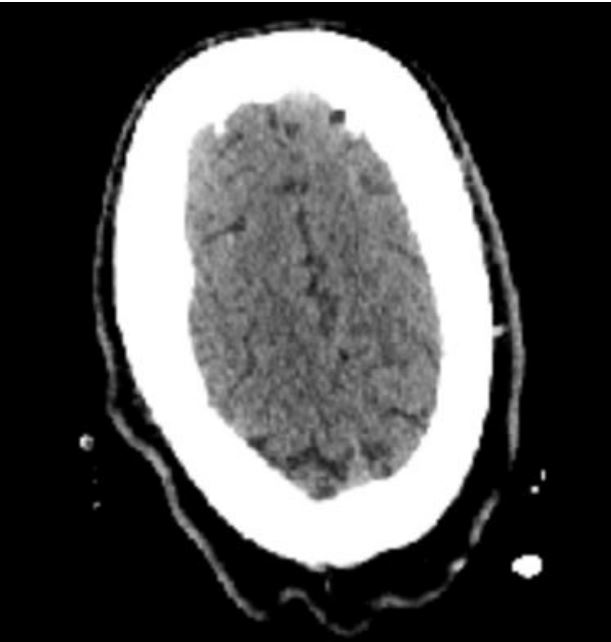

We present a case of a 32-year-old male who presented to the hospital after a motor vehicle accident resulting in multiple facial bone fractures, displaced right third and fourth lateral rib fractures, right lung contusion, right apical pneumothorax, and hemothorax (Figure 1). The patient underwent multiple surgeries, which included right 4th rib open reduction and internal fixation (ORIF), VATS with right upper lobe wedge resection, mechanical pleurodesis, and chest tube placement. Surgical pathology of the VATS specimen revealed a 2 mm irregular nodule with morphologic and immunohistochemical features favoring a meningothelial nodule (Figures 2 and 3). The immunohistochemical stain was positive for vimentin (Figure 4) and epithelial membrane antigen (EMA) and negative for CD56, progesterone receptor, and cytokeratin. A diagnosis of benign pulmonary meningioma was made. The lesion appeared to be excised entirely on the biopsy specimen. Interestingly, this lung nodule was not visualized on any prior chest X-ray or computed tomography (CT) of the chest and was first noted only on the pathology specimen. CT of the head (Figure 5) and the entire spine did not show any primary brain or spinal meningioma, enabling the diagnosis of primary pulmonary meningioma.

Figure 5: CT head without evidence of dural lesion/meningioma in the brain, confirming that the pulmonary meningioma is ectopic and arising primarily in the lungs.